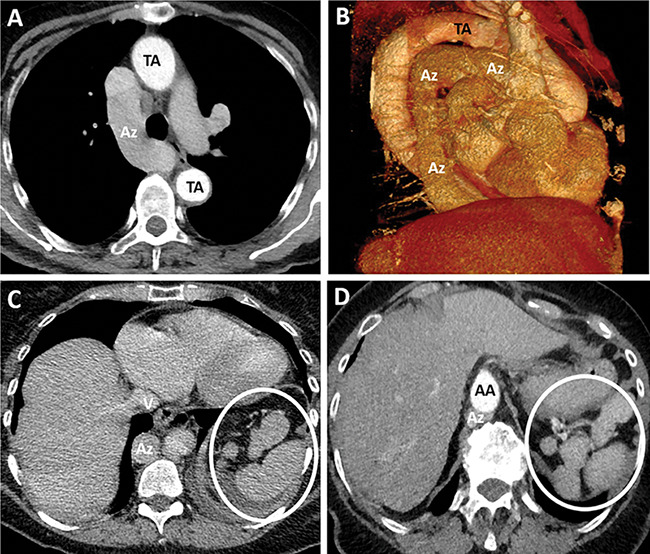

Abstract Image